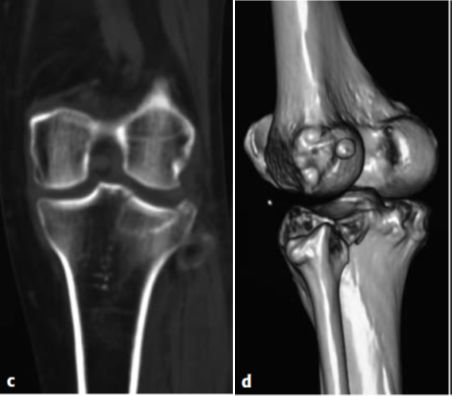

图片图6.8.1-24a-d 胫骨平台双髁骨折一名46岁男性机动车车祸时右腿受伤a  术前X线正、侧位;b  胫骨平台的轴位片;c  骨折的三维重建;d  术后X线正、侧位片